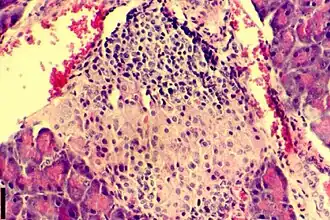

В основе патогенетического механизма развития диабета 1-го типа лежит недостаточность выработки инсулина эндокринными клетками (β-клетки островков Лангерганса поджелудочной железы). Диабет 1-го типа составляет 5—10 % всех случаев диабета[14], чаще развивается в детском или подростковом периоде. Для этого типа диабета характерно раннее проявление симптомов, которые быстро прогрессируют с течением времени. Единственным методом лечения являются пожизненные инъекции инсулина, нормализующие обмен веществ пациента. Без лечения диабет 1-го типа быстро прогрессирует и приводит к возникновению тяжёлых осложнений, таких как диабетическая кардиомиопатия, инсульт, почечная недостаточность, диабетическая ретинопатия, диабетическая язва стопы, кетоацидоз и диабетическая кома, которые приводят к инвалидности или заканчиваются смертью пациента[15].

Дефицит инсулина в организме развивается вследствие недостаточной его секреции β-клетками островков Лангерганса поджелудочной железы.

- Активный аутоиммунный инсулит. Титр антител высок, уменьшается количество β-клеток, снижается секреция инсулина.

- Клиническая манифестация диабета, в том числе с возможным эпизодом «медового месяца» (периода ремиссии в развитии диабета, который характеризуется повышением количества инсулина вырабатываемого бета-клетками). Секреция инсулина резко снижена, так как погибло более 90 % β-клеток.

- Полная деструкция β-клеток, полное прекращение секреции инсулина.

Исследователи из Калифорнийского университета в Сан-Франциско смогли превратить человеческие стволовые клетки в зрелые инсулин-продуцирующие клетки (бета-клетки). Замена этих клеток, которые разрушаются у пациентов с диабетом T1, долгое время была мечтой о регенеративной медицине. Ученые не могли понять, как можно вырастить бета-клетки в лабораторных условиях так, чтобы они работали так же, как у здоровых людей. Ключом к получению искусственных бета-клеток стал процесс их формирования в островки Лангерганса у здорового человека. Авторы метода воспроизвели этот процесс в лабораторных условиях: они искусственно разделили частично дифференцированные стволовые клетки поджелудочной железы и преобразовали их в островковые кластеры. После чего развитие клеток ускорилось. Бета-клетки стали реагировать на уровень сахара в крови сильнее, чем зрелые инсулин-продуцирующие клетки. Также вся «окрестность» островка, включая менее изученные альфа- и дельта-клетки, начали развиваться так, как никогда не получалось сделать в лабораторных условиях.[24]